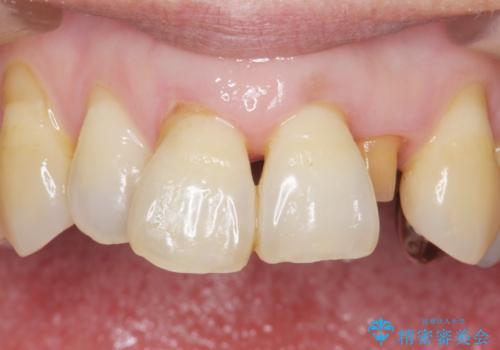

入れ歯も抵抗があるとのことから、相談を重ね、今の状態では保存不可能な下の前歯(左下2)を抜去し、ブリッジや連結補綴により動揺を抑えることにしました。

また、咬み合わせが反対になっている上の前歯(左上2)も補綴で形を変えることにより、咬合を改善しました。

気にされていた前歯と奥歯の動揺がなくなったことと自然な仕上がりに喜んで頂けました。